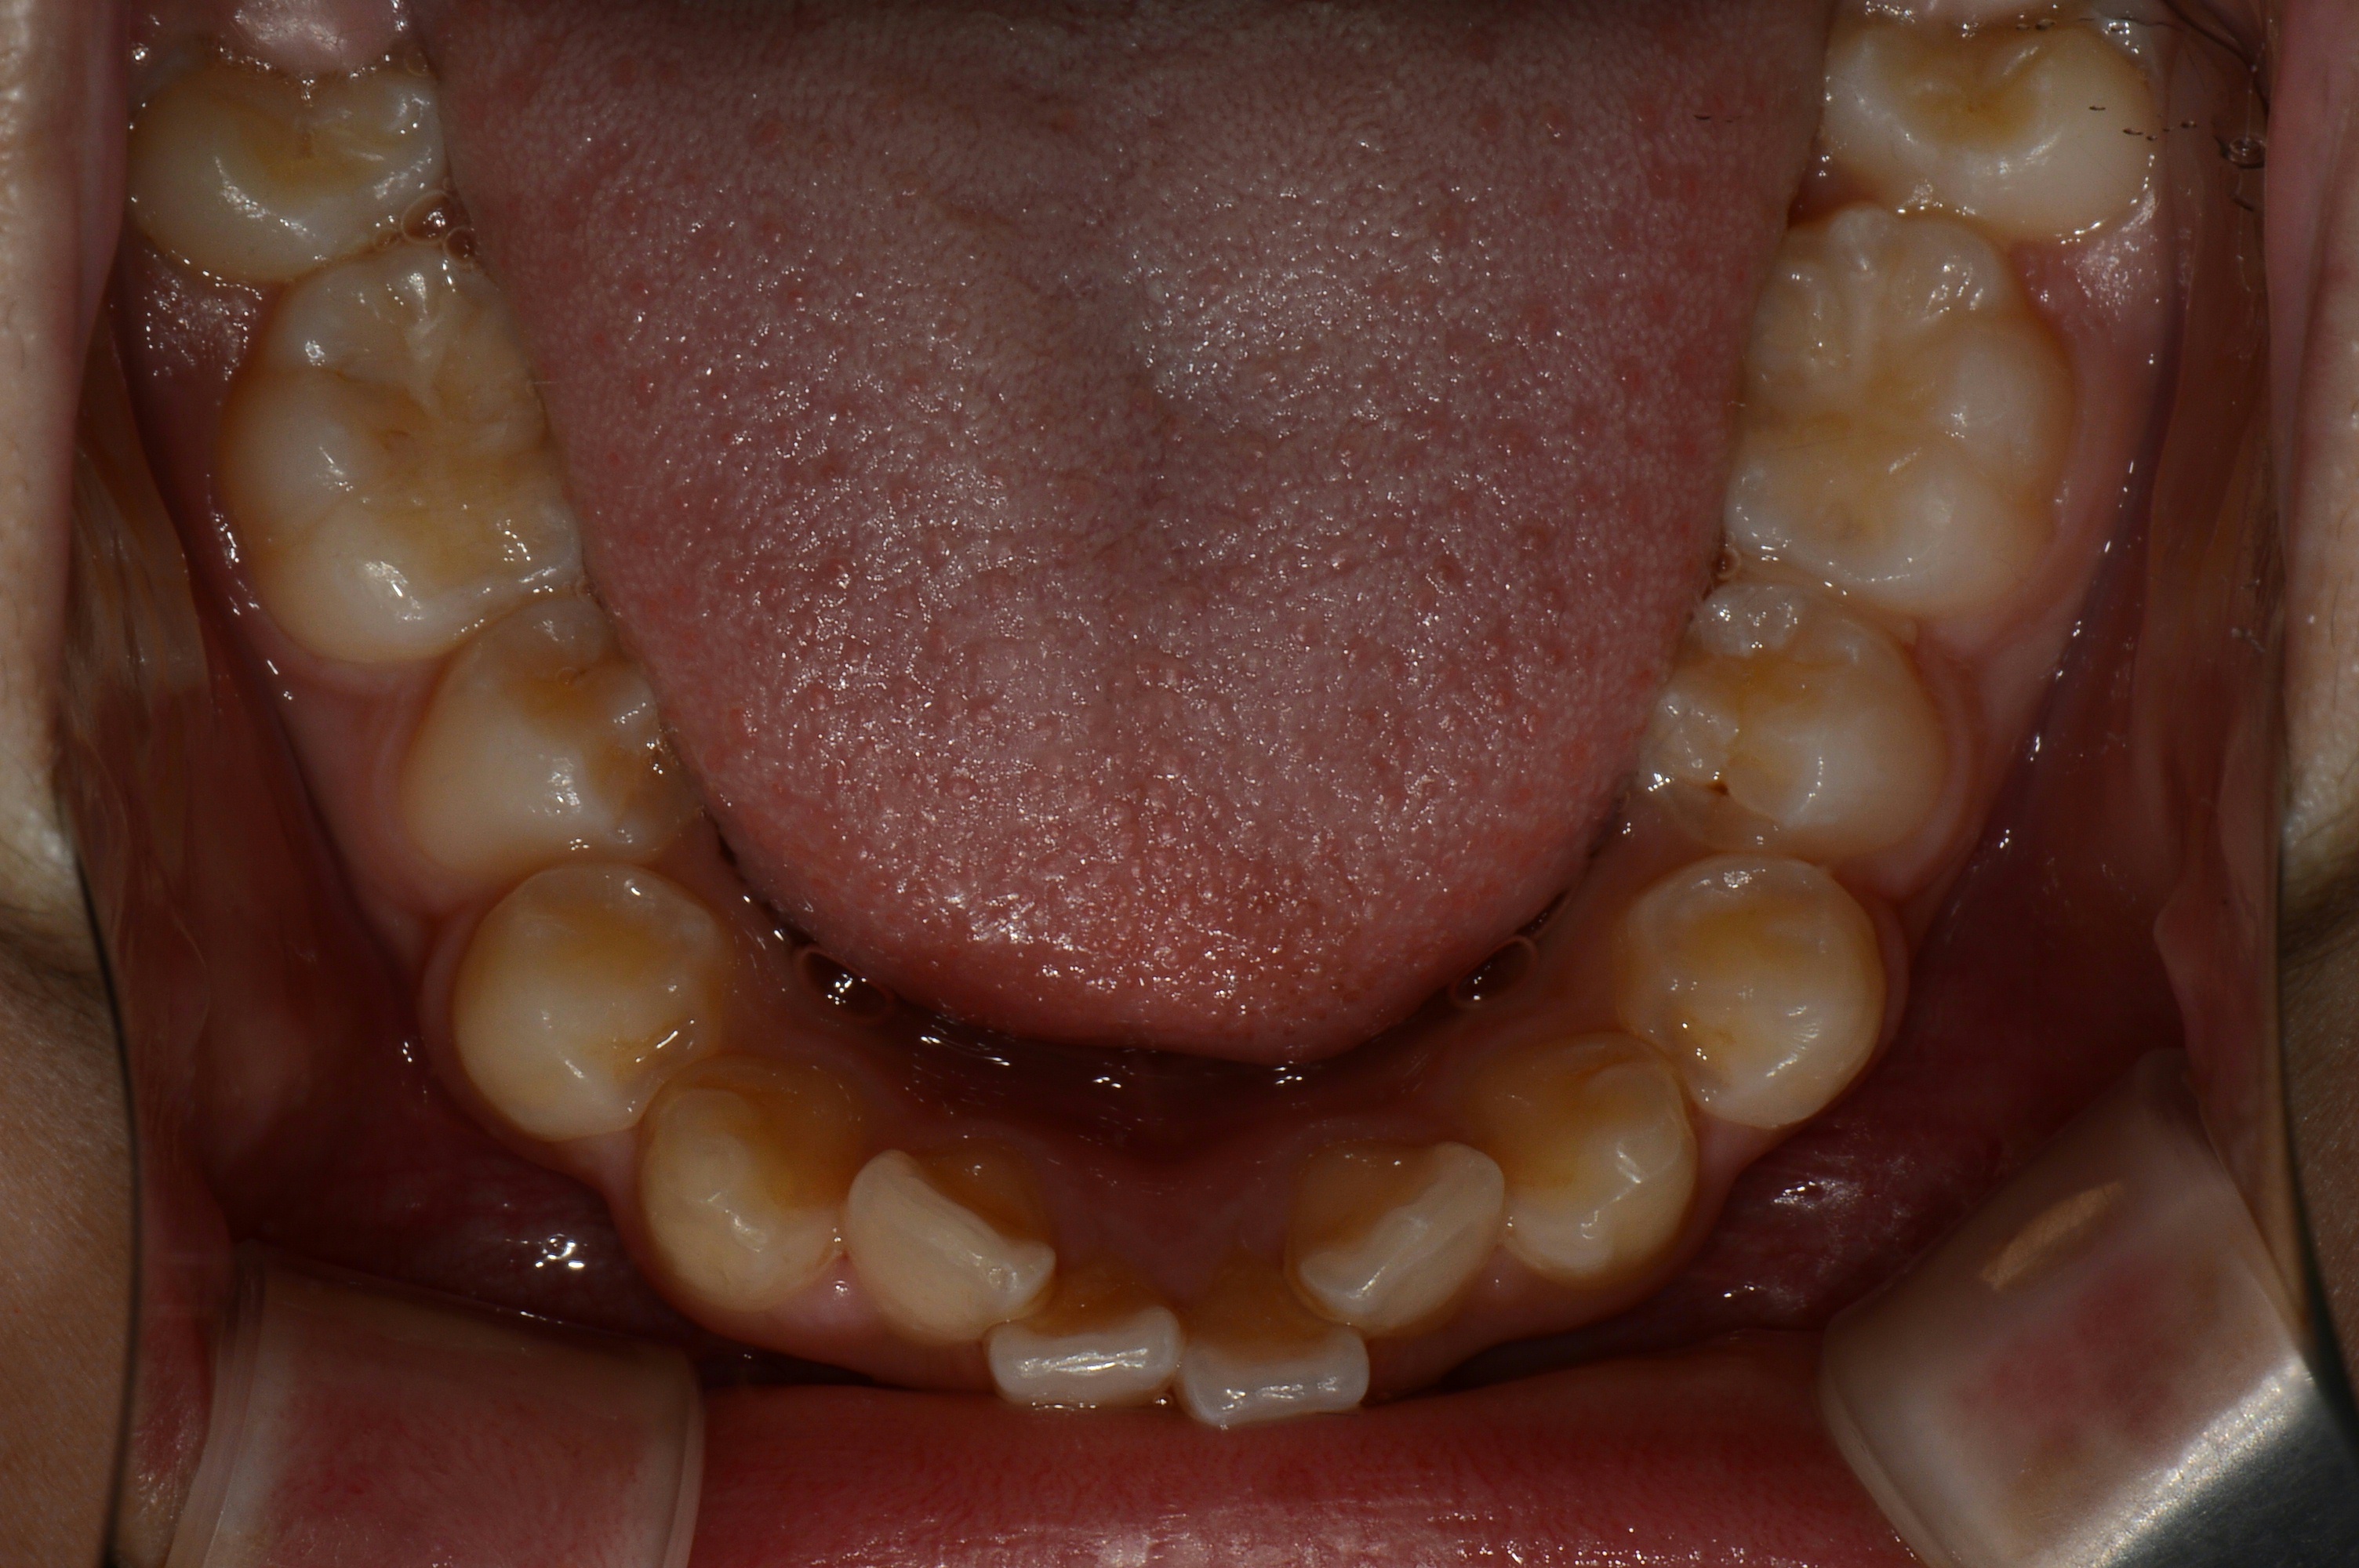

치료 전 사진입니다.